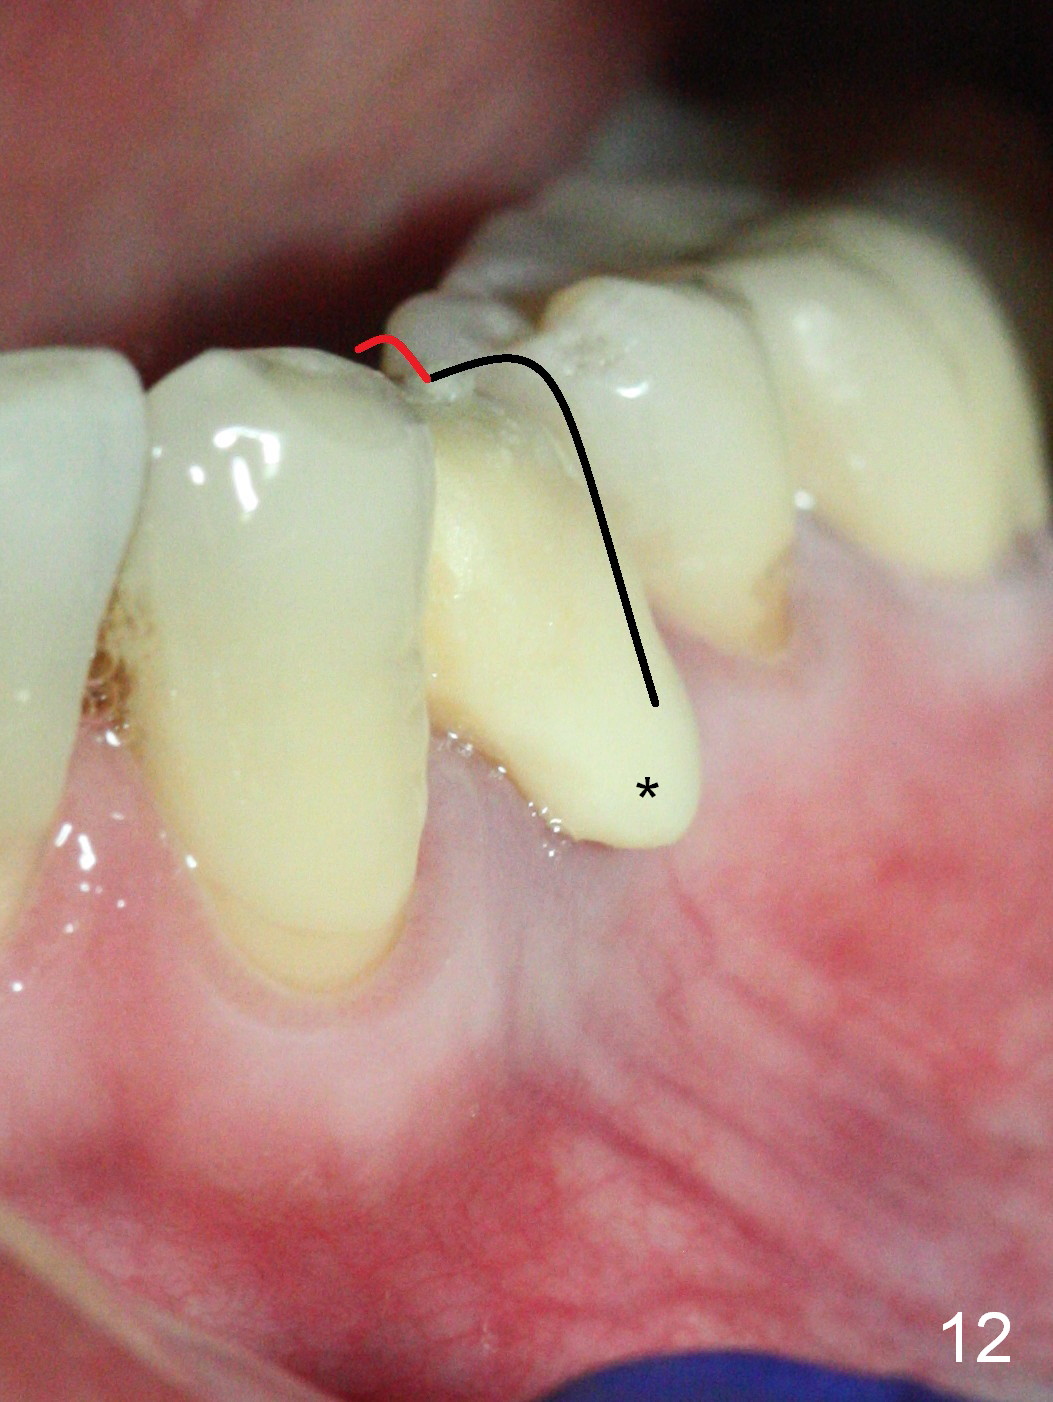

The implant seems to have osteointegrated 4 months postop (Fig.9).  When a permanent crown is fabricated, it should have normal occlusal and buccal contour (from Fig.11 (provisional) to 12 red and black curved lines) as well as the buccal cervical extension (Fig.12 to cover the buccal gingiva (Fig.10 *).  If the lingual margin of the abutment is too prominent, return the case and the abutment will be changed to the one with 2 mm cuff (existing 3 mm).  The lingual margin of the abutment will be trimmed.  The patient is not pleased with the short buccal margin of the crown after cementation (Fig.13).  In fact the provisional should have been fabricated so that the its buccal margin should be subgingival and within the gingival outline.  It may prevent buccal plate collapse.  In fact the crown dislodges 1 year post cementation.  The lingual margin is prep lower to increase the abutment height.  Impression is taken.  Although the access hole is unnecessary for cementation, it acts as an escape hole so that there is no excess cement cervically (Fig.14-18).